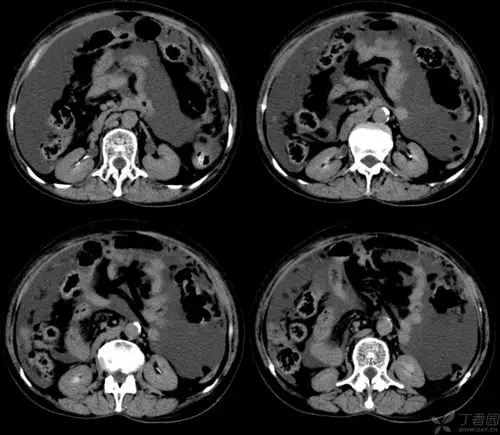

腹腔积液的良恶性表现与鉴别